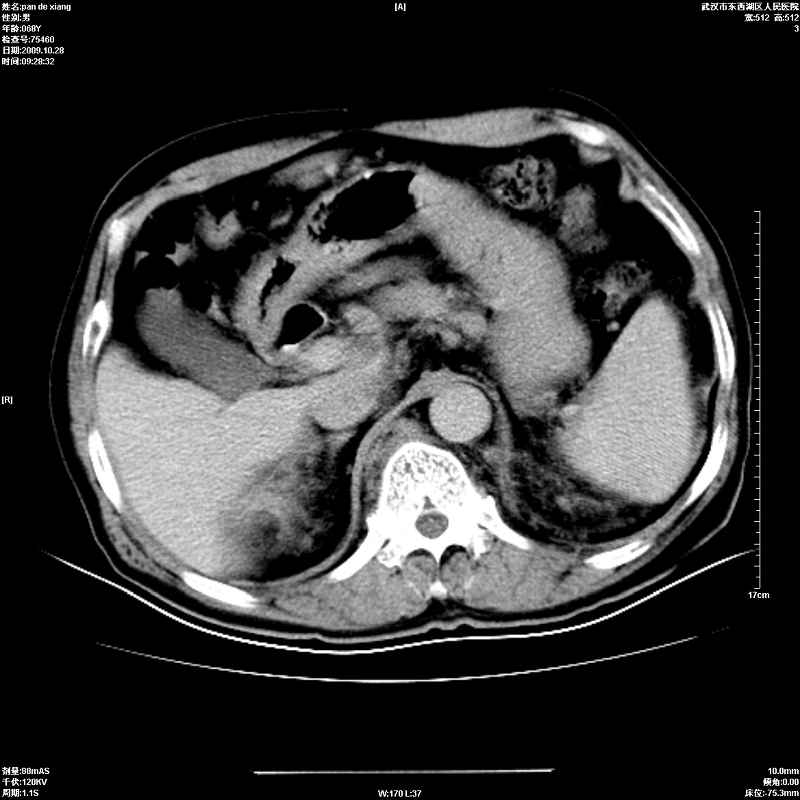

以下是引用杀毒软件在2009-10-28 20:41:00的发言:[br]结合临床考虑---白血病双肾改变或淋巴瘤。

以下是引用zxl51642在2009-10-29 9:59:00的发言:[br]结合临床“单克隆免疫球蛋白血症”,考虑双肾为继发损害并肾功能不全(尿中大量igg及少量iga、igm等大分子免疫球蛋白滤出所致继发损害),椎前软组织肿块为髓外造血。与浆细胞瘤有区别,平扫时有战友说的很清楚。